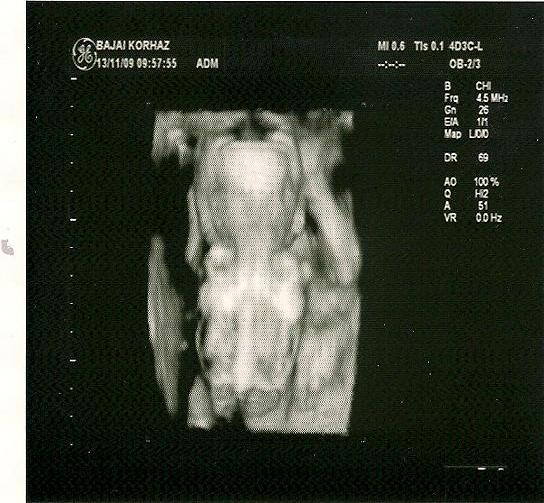

Iner- Gondolom, hogy varod mar az AFP-t, de ha szar eredmeny jön ki, az ugy sem igaz....ha viszont jo, akkor tuti minden rendben van

Mar lassan jön az amnio es veget er ez a nehez idöszak szamotokra